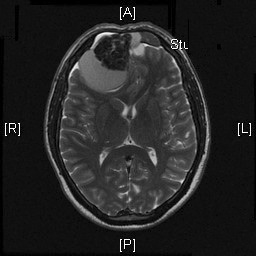

Radiologic Images of the Case: CT scan demonstrated a large midline mixed density mass with fat density that occupies the ethmoid sinus with extension through the cribiform plate into the inferior portion of the anterior cranial fossa. The mass is 5.1 x 3.2 cm in greatest dimension (Panel A). Bone windows of CT scan demonstrated bone expansion suggestive of remodeling (Panel B). On MRI, spoiled gradient recalled (SPGR ) post contrast images showing mass is either avidly enhancing or bright on T1 precontrast. (Panel C). The mass hypointense signal intensity compared to brain parenchyma with surrounding areas of increased signal (suggestive of entrapped mucus) on T2 weighted images (Panel D and E).